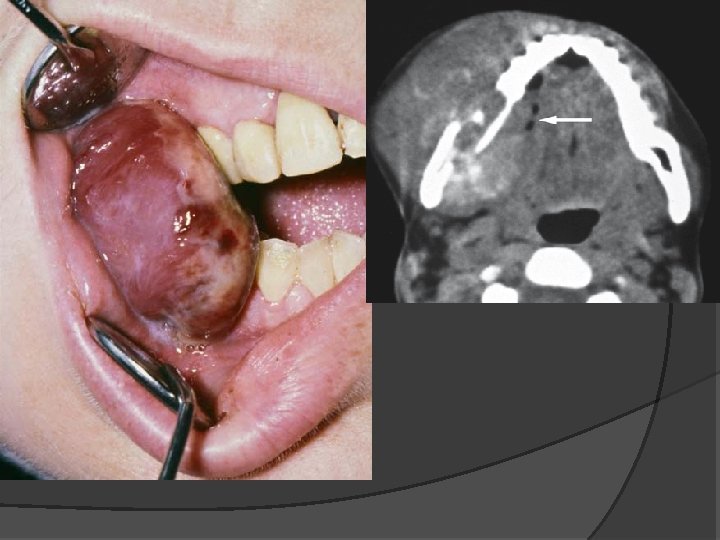

Clinical photograph shows leukoplakia that transformed to gingival cancer Intraoral panoramic view shows diffuse bone destruction

Non-Hodgkin’s lymphoma, maxilla; 49 -year-old male painless swelling